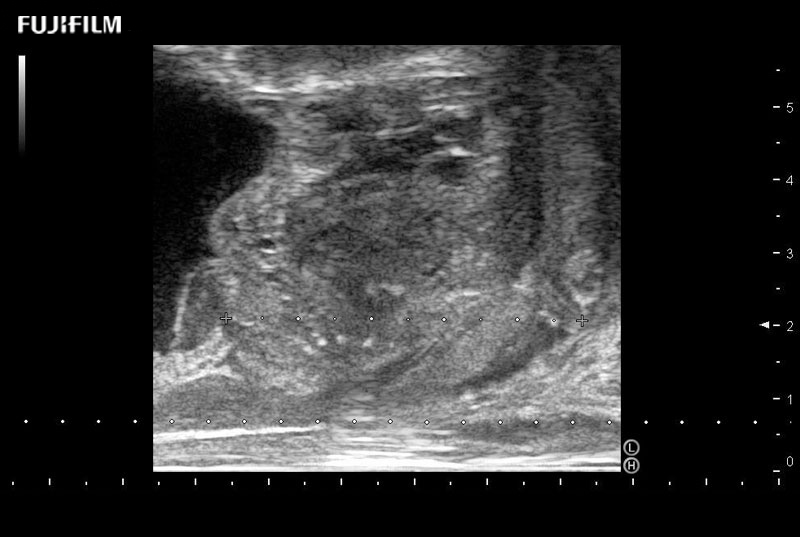

Ideal transducer for Transperineal Biopsy, Hydrogel Spacer Placement, Brachy LDR & HDR, Cryo, and MPMRI procedures.

Main Specifications: